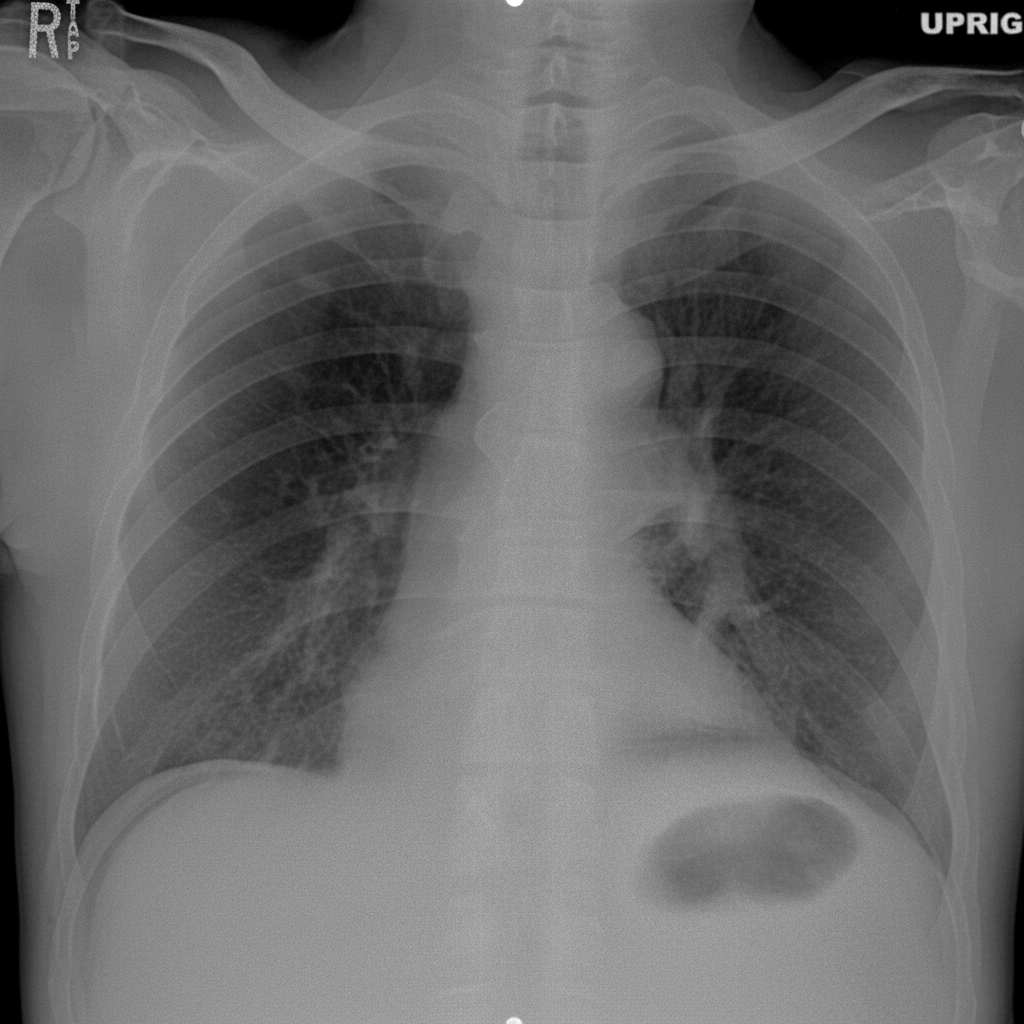

What does the X-ray film show?

Explanation: ***Perforated abdominal viscus*** - X-ray findings in perforated viscus include **free air under the diaphragm** (pneumoperitoneum) on erect chest/abdominal X-ray, which is the hallmark sign - **Rigler's sign** (both sides of bowel wall visible) and **football sign** (large amount of free air outlining abdominal organs) may be seen - Common causes include **perforated peptic ulcer**, perforated appendix, or bowel perforation from trauma or ischemia - This represents a **surgical emergency** requiring immediate intervention *Intestinal obstruction* - Shows **dilated bowel loops** with **air-fluid levels** on erect X-ray - **Absent or reduced gas in distal bowel** in complete obstruction - Does not typically show free intraperitoneal air unless there is associated perforation - Multiple air-fluid levels at different heights distinguish it from perforation *Pneumoperitoneum* - While pneumoperitoneum (free intraperitoneal air) is a **radiological finding**, it is not a diagnosis in itself - It is a **sign** that indicates perforation of a hollow viscus - "Perforated abdominal viscus" is the more complete clinical diagnosis that explains the cause of pneumoperitoneum *Right hydropneumothorax* - Shows **air-fluid level in the pleural space** (thoracic cavity, not abdominal) - Air appears as **radiolucency in upper part** with fluid level below in the pleural cavity - Caused by trauma, infection (empyema with gas-forming organisms), or iatrogenic causes - Would be seen in the **chest**, not abdomen, and would not show subdiaphragmatic free air